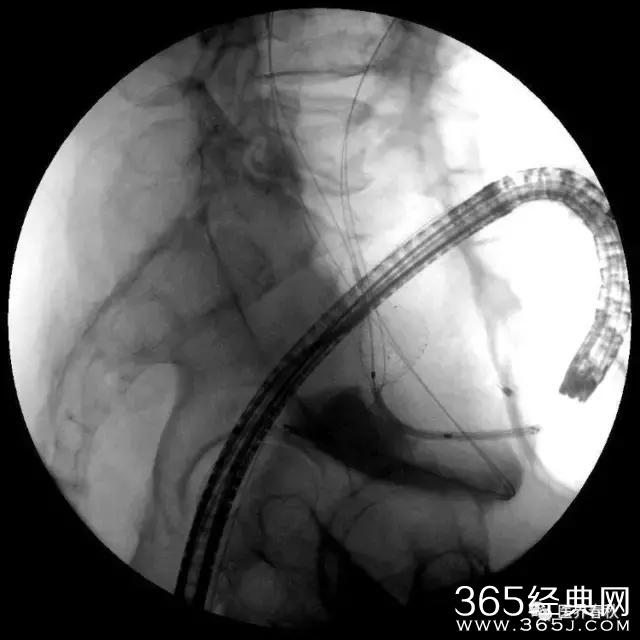

对出血部位的血管进行栓塞治疗

高难度狭窄处U型弯结肠支架植入术

支架成功释放后